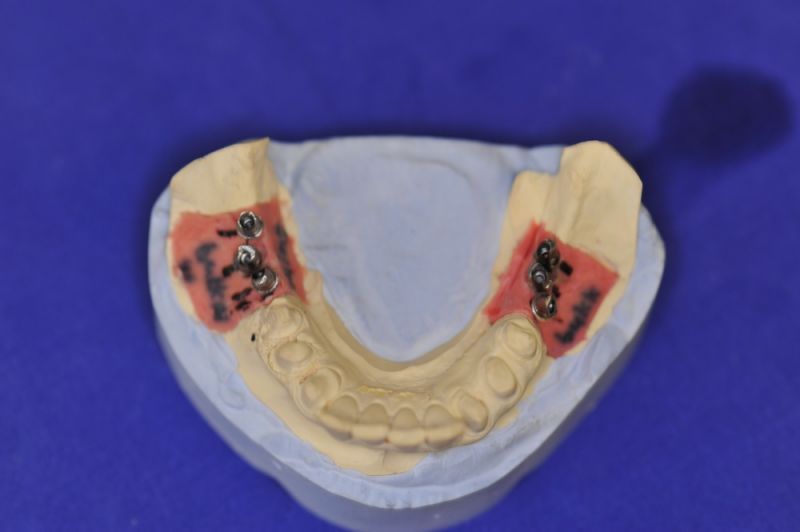

Geplant waren zwei Implantate in regio 6 und 7 des Unterkiefers. Trotz aller Planungen stellte sich intraoperativ heraus, dass zwei Implantate mit dem nötigen Durchmesser nicht in den extrem schmalen Kieferknochen des Unterkiefers einzubringen waren.

Also wurde intraoperativ umentschieden die Krafteinwirkung von geplanten zwei Normalimplantaten auf drei kleinere Implantate umzuleiten.

Es wurden sechs Implantate inseriert und diese wuchsen, trotz vielerlei Bedenken knöchern ein.

Nun stellte sich heraus, dass der Abstand zwischen den Implantaten sehr gering war, weil die Einschubrichtungen der Aufbauten sich zum Teil gegenseitig im Wege standen. Konfektionierte Teile mussten individuell umgeschliffen werden, dabei das Ziel, den Biss korrekt einzustellen nicht aus dem Auge zu verlieren.

Heute war nun Gerüsteinprobe, mit all den Problemen der Umsetzung zwischen Laborsituation und Mundsituation. Siehe Stichpunkt "Schnittstellenproblematik"! was bei Zähnen, auf Grund deren Eigenbeweglichkeit im Kieferkochen kein Problem wäre, ist bei drei unbeweglichen Implantaten ein Riesenproblem. Darüber spricht nur in aller Regel Niemand! Es musste viel fein nachgearbeitet werden.